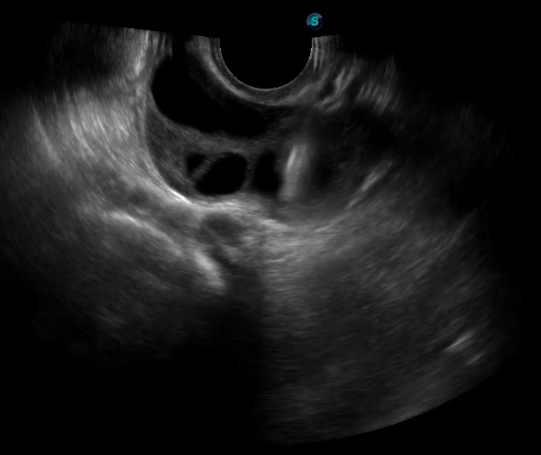

取卵臨床圖

傳統(tǒng)腔內探頭采用直柄設計,在搭配穿刺架使用時,手術空間小,不易操作;生殖專用的曲柄探頭,探頭柄采用彎曲成角度設計,可實現(xiàn)監(jiān)視、取卵兩不誤,搭載穿刺架時,可以清晰顯示穿刺針的進針過程、深度和位置,實時監(jiān)視取卵全過程,保障取卵操作精準與安全。